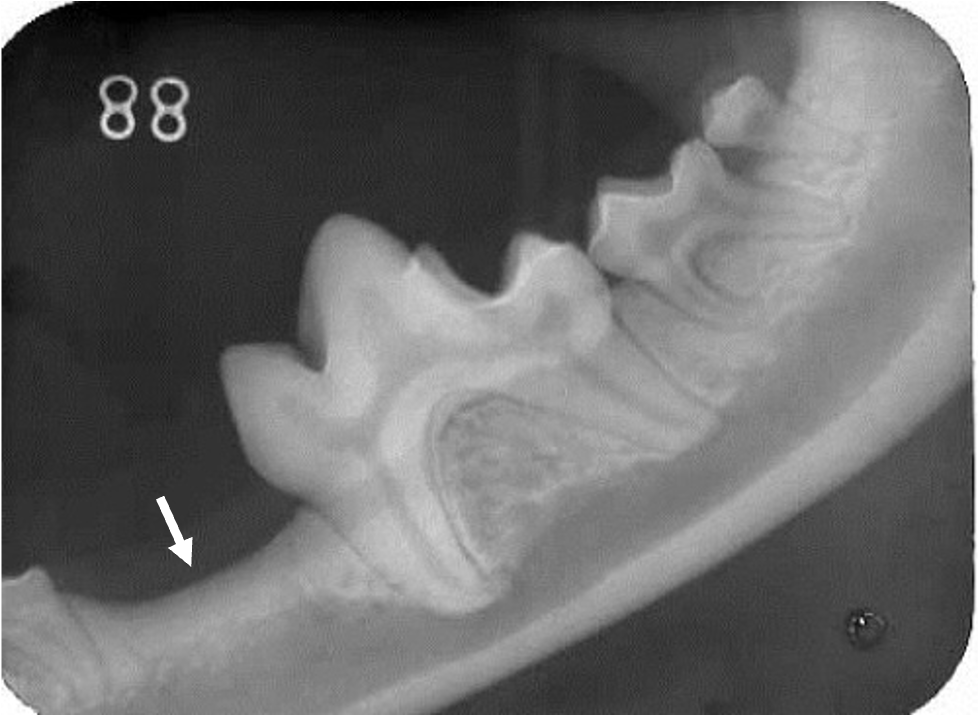

歯が生えていないように見えます

レントゲン写真では永久歯が埋まっています

埋伏歯は将来的に嚢胞化したり、腫瘍化することがあるため、注意が必要です